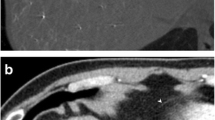

Case 1: full coronal (a) and sagital medial (b) MPR views obtained during the arterial phase of contrast enhanced abdominal MDCT. A large amount of hemorragic ascitis (grey arrow) with massive fresh clots (white arrows) is found in the peritoneal cavity. An active bleeding puddle (small black arrows) is found just on the midline of the anterior epigastric area straddling the demarcation between properitoneal fat and the peritoneal cavity. It is situated just in front of the laparotomy site